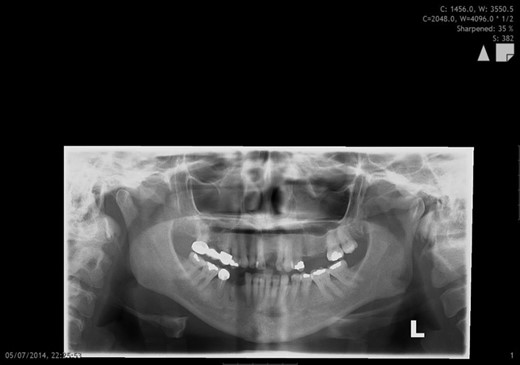

A 53-year-old female initially presented to the emergency department following an assault in which she sustained a punch to the left side of her jaw. Her medical history of note was type 2 diabetes, hypertension and hypercholesterolaemia. Clinical and radiographical examination revealed a left high condylar head fracture (Fig. 1). Her occlusion was stable and non-surgical management was employed. On 2-month review, she complained of a persistent, painless, slow growing mass in the left pre-auricular area. Clinical examination revealed a soft, mobile, non-tender, non-fluctuant, regular mass within the left parotid gland with normal overlying skin and normal sensation. There was no associated cervical lymphadenopathy and facial nerve function was intact.

Orthopantomographic image showing a left high condylar head fracture and a stable occlusion with adequate posterior contact.